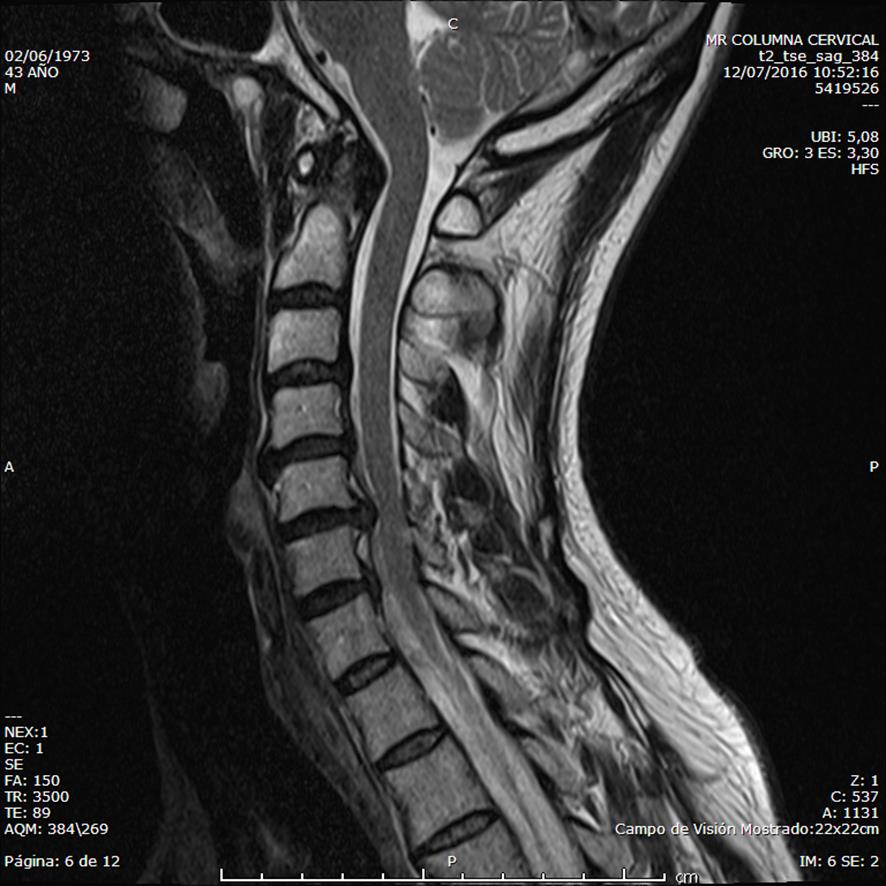

La resonancia magnética es la prueba más sensible para concretar el diagnóstico y definir el tipo, tamaño, situación de la hernia y comprobar si hay una compresión de la raíz nerviosa y de la médula.